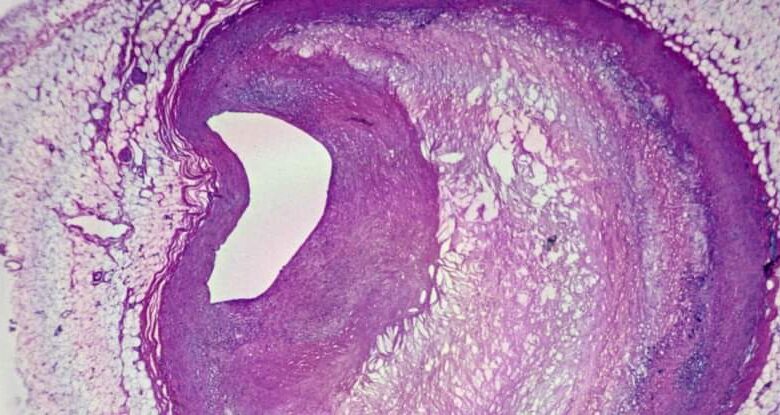

وكانت الجسيمات البلاستيكية مرئية أيضًا تحت مجاهر قوية: لاحظ الباحثون شظايا بلاستيكية ذات حواف خشنة داخل الخلايا المناعية التي تسمى البلاعم، وداخل اللويحات الدهنية. وبفحص عينات الأنسجة، وجد الفريق أيضًا مستويات أعلى من علامات الالتهاب لدى المرضى الذين لديهم جسيمات بلاستيكية دقيقة في لويحاتهم.

لوحة مكونة من صورتين بالأبيض والأسود تظهر جزيئات بلاستيكية خشنة، مميزة بالسهام، في أقسام الأنسجة، والتي يتم عرضها تحت المجهر.

وشوهدت جزيئات بلاستيكية خشنة داخل الخلايا البلعمية ورواسب الأنسجة الدهنية، التي تم إزالتها من الشرايين المسدودة.